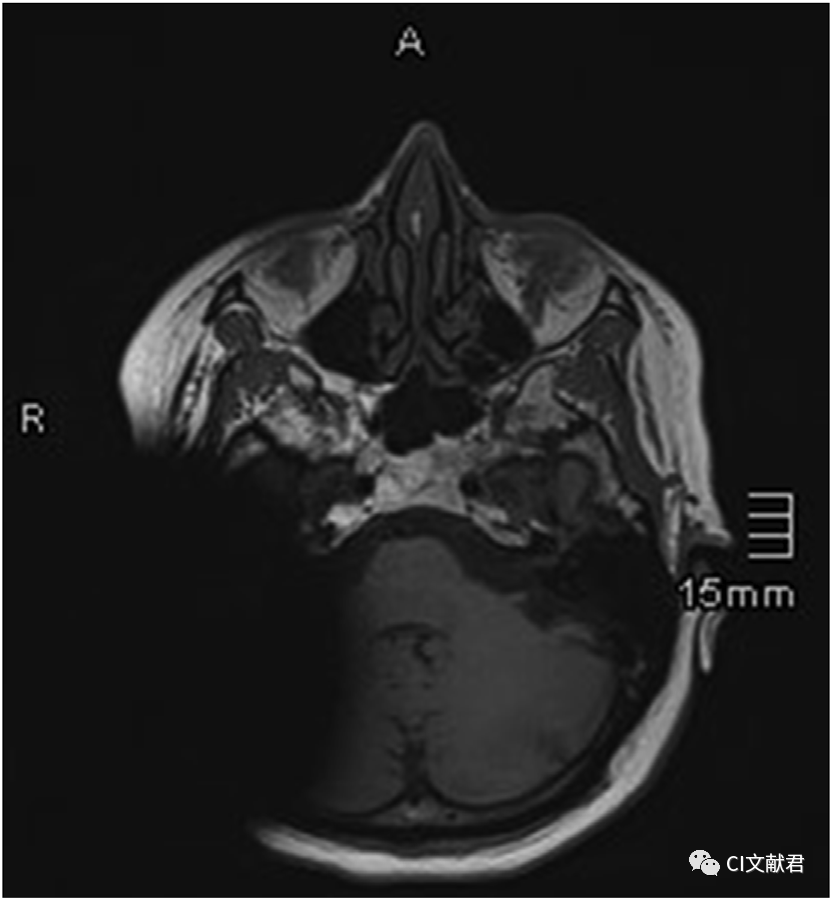

普通扫描技术

图片中的患者接受了人工耳蜗植入(奥地利MED-EL Mi1200 Synchrony)和前庭神经鞘瘤切除同期手术。在术后半年因复查肿瘤情况行磁共振检查。在磁场强度1.5T的磁共振机上分别进行了2次扫描,第一张图为采用普通扫描技术获得的影像,第二张图为采用伪影消除扫描技术获得的影像。可以看出人工耳蜗磁铁和金属材料造成的伪影几乎完全消除。而患者没有因此接受任何形式的二次手术。